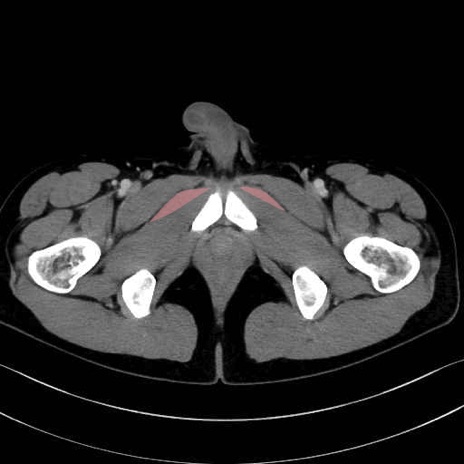

短内転筋(Adductor brevis) のCT画像の解剖

短内転筋 (Adductor brevis)